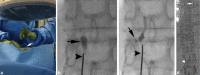

Traumatic chylothorax occurs more often now than in historic reports. In part, this is due to the increased ability to perform more advanced and aggressive thoracic resections and cardiovascular surgeries as well as the improved mortality of cancer patients. If untreated, chylothorax can result in significant morbidity and mortality, particularly in patients with underlying malignancy. Thoracic duct embolization for chylothorax was the first successful lymphatic intervention and has been performed for over 20 years. An overview of the clinical and technical approach to thoracic duct embolization for traumatic chylothorax is presented in addition to a review of outcomes.